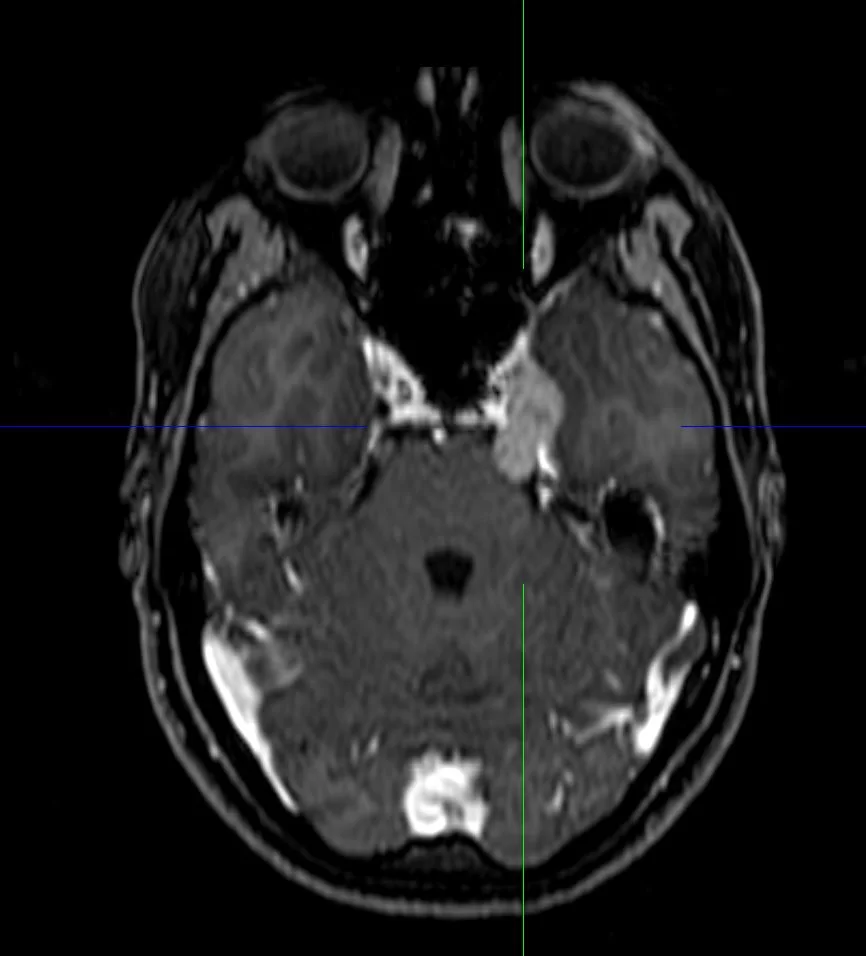

Επιδερμοειδής όγκος δεξιάς γεφυροπαρεγκεφαλιδικής γωνίας

Ασθενής 19 ετών με γνωστή χωροκατακτητική εξεργασία (επιδερμοειδες γεφυροπαρεγκεφαλιδικής γωνίας δεξιά) με προοδευτικά σημαντική αύξηση μεγέθους. Νευρολογικά ακέραιος. Ο απεικονιστικός έλεγχος με μαγνητική τομογραφία ανέδειξε